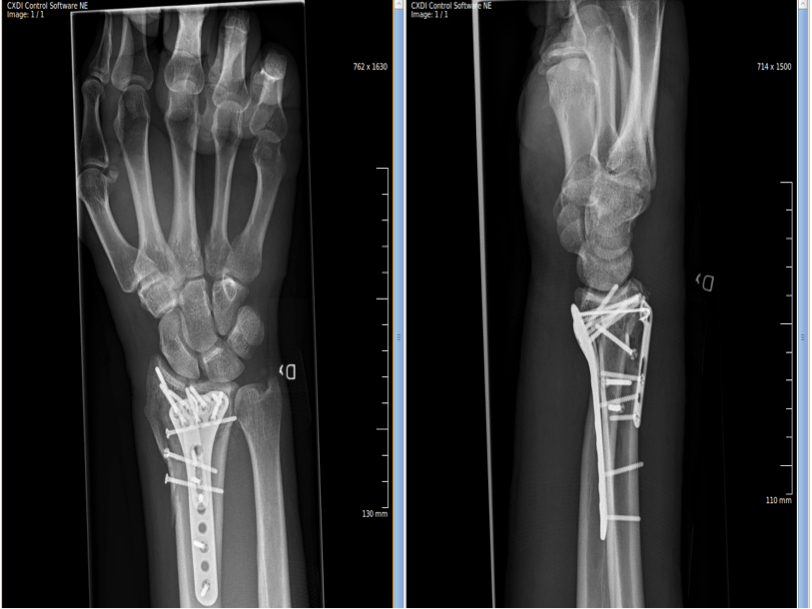

Wrist Fracture Surgery GlobeHealer Define Fracture Quizlet Describe the steps involved in bone repair. A fracture is a break in a bone. Study with quizlet and memorize flashcards containing terms like define fracture, s/s of a fracture, emergency management for a fracture. A fracture is a broken bone. Right or left side involved;. (a) closed fracture, (b) open fracture, (c) transverse fracture, (d) spiral fracture, (e) comminuted. Define Fracture Quizlet.